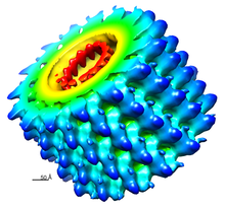

Reoviruses (呼吸道腸道病毒)

-

ds RNA

- 多段

-

double-layered capsids

- 20 面

- intermediate/ infectious subviral particle (ISVP)

- 中外層的capsid (σ3/VP7)在腸道被蛋白酶分解

- σ1/VP4 被切割產生 ISVP

- VP4 → VP5,VP8

-

無套膜

- 先去 ER 再裂解

-

丟 RNA(+)出來做蛋白

- 口糞傳染

Orthoreovirus 會感染人類,所以 Reoviruses 就是 Orthoreovirus,而 Reoviridae 指所有

Rotavirus(輪狀病毒)

- 11段 RNA

- 有疫苗(減毒)

- 寶寶的第一個副食品!

- 2,4,6 月

- 疾病

- 嬰兒拉肚子,嚴重水洩

- 小腸絨毛變短變鈍

- 嘔吐、腹瀉、發燒和脫水

- 腸胃道及呼吸道症狀?